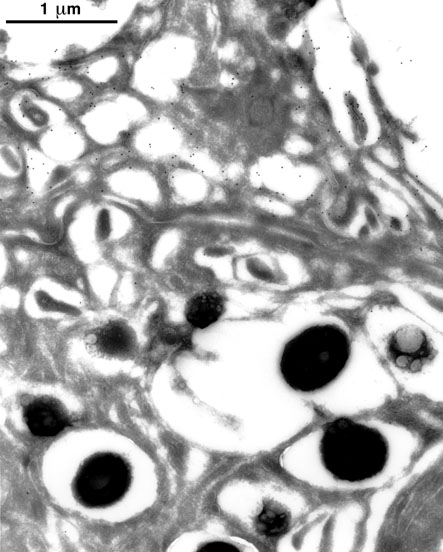

Figure 3. Immunoelectron micrograph of human ciliary body stained with rabbit antiserum against carboxy-terminal peptide of human placenta amine oxidase

Sections of human ciliary body produced by ultracryomicrotomy were stained with rabbit antiserum against the carboxy-terminal peptide of human placenta amine oxidase and a colloidal-gold-conjugated secondary antibody. Numerous colloidal gold particles (black dots) are localized to the plasma membrane of an inner epithelial cell (top half of micrograph), visible in may areas as a thin, lucent line. A small number of gold particles are localized to the surface of an adjacent outer epithelial cell (bottom half of micrograph) and to cytoplasm of both cells. The latter cell contains numerous electron-dense pigment granules; no significant staining of the granules is present. The clear halos surrounding the granules and the small, bubble-like lucencies within some of them are most likely artifacts of processing and embedding of the sections.